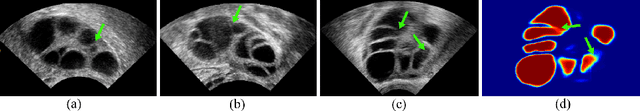

Abstract:Ultrasound (US) image segmentation embraced its significant improvement in deep learning era. However, the lack of sharp boundaries in US images still remains an inherent challenge for segmentation. Previous methods often resort to global context, multi-scale cues or auxiliary guidance to estimate the boundaries. It is hard for these methods to approach pixel-level learning for fine-grained boundary generating. In this paper, we propose a novel and effective framework to improve boundary estimation in US images. Our work has three highlights. First, we propose to formulate the boundary estimation as a rendering task, which can recognize ambiguous points (pixels/voxels) and calibrate the boundary prediction via enriched feature representation learning. Second, we introduce point-wise contrastive learning to enhance the similarity of points from the same class and contrastively decrease the similarity of points from different classes. Boundary ambiguities are therefore further addressed. Third, both rendering and contrastive learning tasks contribute to consistent improvement while reducing network parameters. As a proof-of-concept, we performed validation experiments on a challenging dataset of 86 ovarian US volumes. Results show that our proposed method outperforms state-of-the-art methods and has the potential to be used in clinical practice.

Abstract:Ultrasound (US) is widely accepted in clinic for anatomical structure inspection. However, lacking in resources to practice US scan, novices often struggle to learn the operation skills. Also, in the deep learning era, automated US image analysis is limited by the lack of annotated samples. Efficiently synthesizing realistic, editable and high resolution US images can solve the problems. The task is challenging and previous methods can only partially complete it. In this paper, we devise a new framework for US image synthesis. Particularly, we firstly adopt a sketch generative adversarial networks (Sgan) to introduce background sketch upon object mask in a conditioned generative adversarial network. With enriched sketch cues, Sgan can generate realistic US images with editable and fine-grained structure details. Although effective, Sgan is hard to generate high resolution US images. To achieve this, we further implant the Sgan into a progressive growing scheme (PGSgan). By smoothly growing both generator and discriminator, PGSgan can gradually synthesize US images from low to high resolution. By synthesizing ovary and follicle US images, our extensive perceptual evaluation, user study and segmentation results prove the promising efficacy and efficiency of the proposed PGSgan.